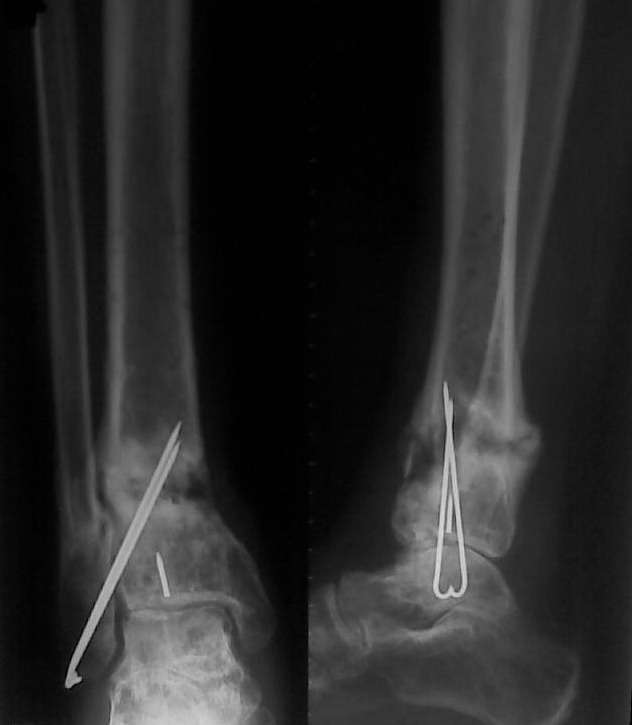

Уважаемые коллеги, обратилась больная 30 года, травма 1 год назад, открытый перелом дистального метаэпифиза левой голени, закрытый перелом левой таранной кости, закрытый перелом наружной лодыжки слева.

Больная была прооперирована в солидном лечебном учреждении был произведен остеосинтез переломов (снимков пока нет). Послеоперационный период осложнился нагноением, конструкции были удалены. На сегодняшний день имеется следующее: по переднее-медиальной поверхности имеется свищ около 5 мм в диаметре с небольшим количеством гнойного отделяемого, конечность опорна, боли при нагрузке практически нет. Нервно - сосудистый статус без патологии. Подошвенное сгибание 10, тыльное 8 градусов. Снимки представлены ниже. Как лучше поступить в данном случае? имеется 2 варианта:

1. Удалить спицы, качественная секвестрнекрэктомия, лаваж полости с последующим заполнением её цементными бусами с антибиотиком. С целью профилактики перелома наложить простейший АВФ из двух колец. Через 2-4 недели (при благоприятном течении процесса) удалить бусы и заполнить полость аутографтом. Что смущает при этом варианте: малый размер полости 20 х 30 мм - мало цемента с антибиотиком - недостаточная концентрация антибиотика. Кроме того, дефект расположен вблизи сустава, где существует малое количество мягких тканей. Смущает так же состояние таранной кости.

2. Выполнить резекцию очага с последующим замещением дефекта по Илизарову. Больная и родственники не совсем в восторге от этого варианта (длительные сроки, неудобства, связанные с ношением АВФ). Хотя возможно это и лучший вариант. Про таран уже говорилось выше.